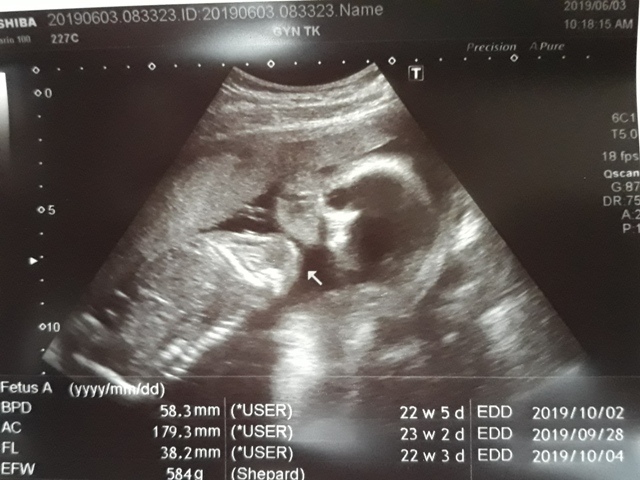

早上十點左右,和小純至澄清醫院做產檢,今日要做的是『妊娠糖尿病』的檢查(一般來說,妊娠糖尿病是24週 - 28週檢查,不過小純今天是第23週又3天,還沒到24週),首先我們先到抽血室去,護理師拿了五瓶裝的美達妍注射液讓小純喝,喝完之後一個小時以後再進行抽血。來之前小純有跟我說過,驗妊娠糖尿病要喝很甜的 糖水,但她今天喝了,感覺還好,不會很甜。

近五次產檢資料統計

| 日期/項目 | BPD | AC | FL | EFW | 心跳 |

| 2019年03月04日 | 無資料 | 無資料 | 無資料 | 無資料 | 無資料 |

| 2019年04月01日 | 28.9mm | 77.9mm | 14.2mm | 107g | 153 |

| 2019年04月29日 | 41.7mm(44%) | 125.7mm(61%) | 28.9mm(103%) | 241g(125%) | 150 |

| 2019年05月22日 | 53.4mm(28%) | 160.6mm(28%) | 34.6mm(20%) | 408g(69%) | 150 |

| 2019年06月03日 | 58.3mm(9%) | 179.6mm(12%) | 38.2mm(10%) | 584g(43%) | 157 |

| BPD:胎兒頭骨橫徑 AC:胎兒腹圍的長度 FL:胎兒大腿骨的長度 EFW:胎兒的體重 括弧內百分比為較上次產檢的成長比例 | |||||

今天關醫師也把4月22日所做的羊膜穿刺及羊水晶片的報告拿給我們,一切都正常。